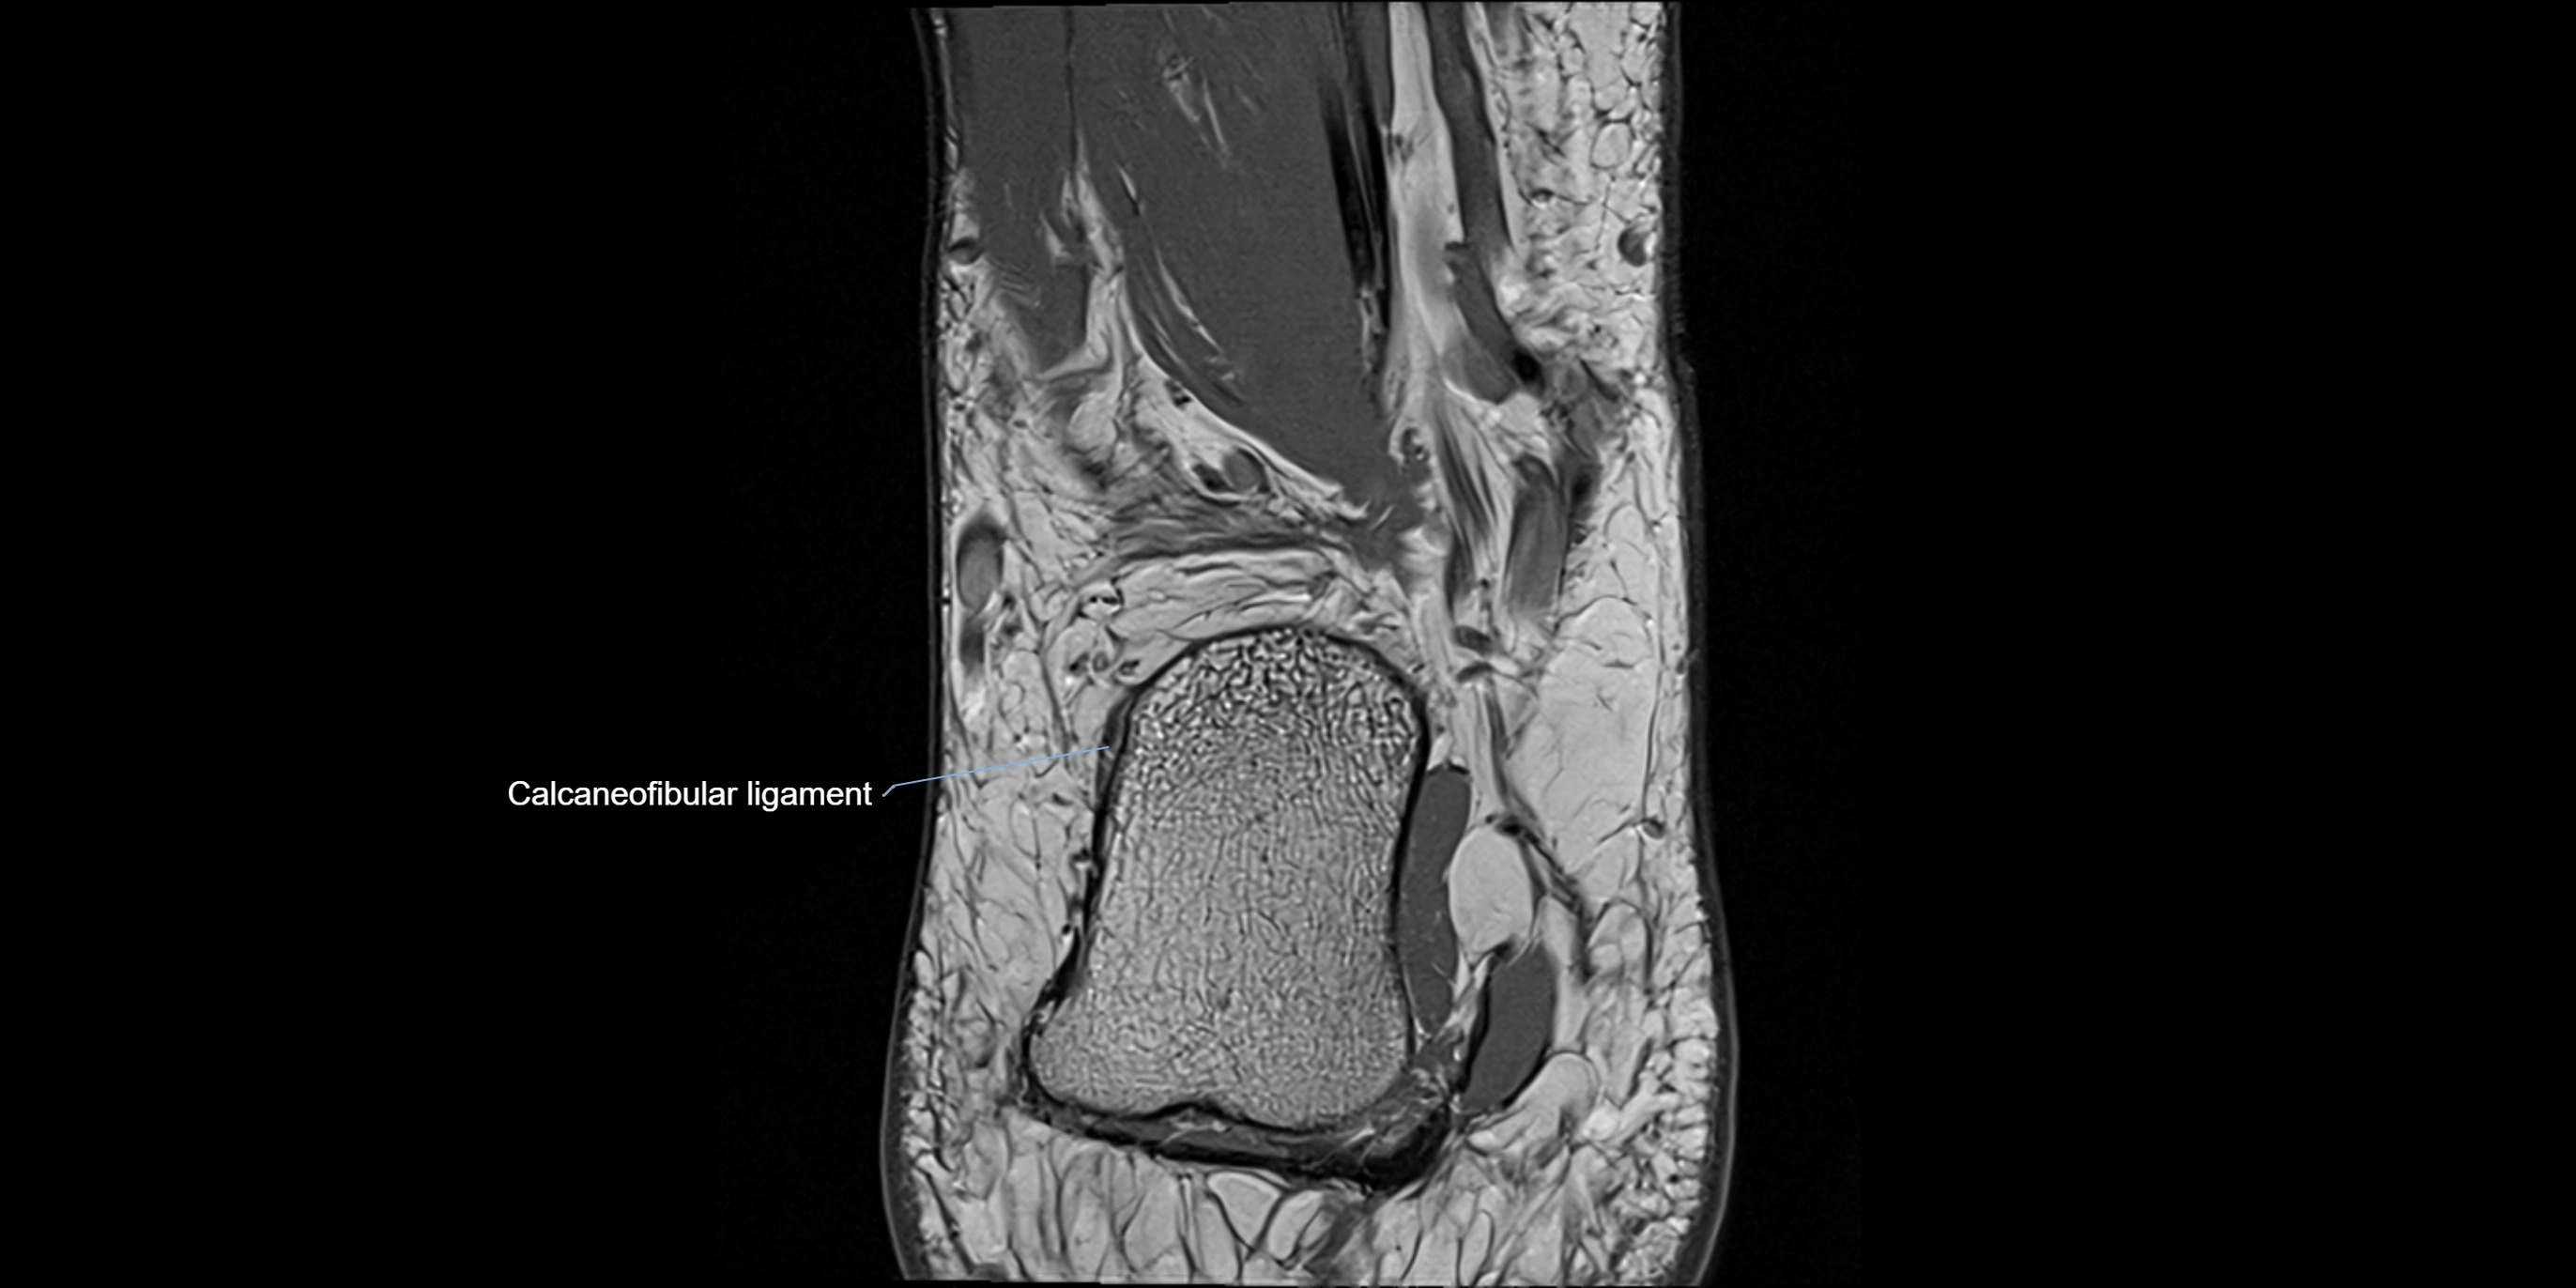

MRI image

image